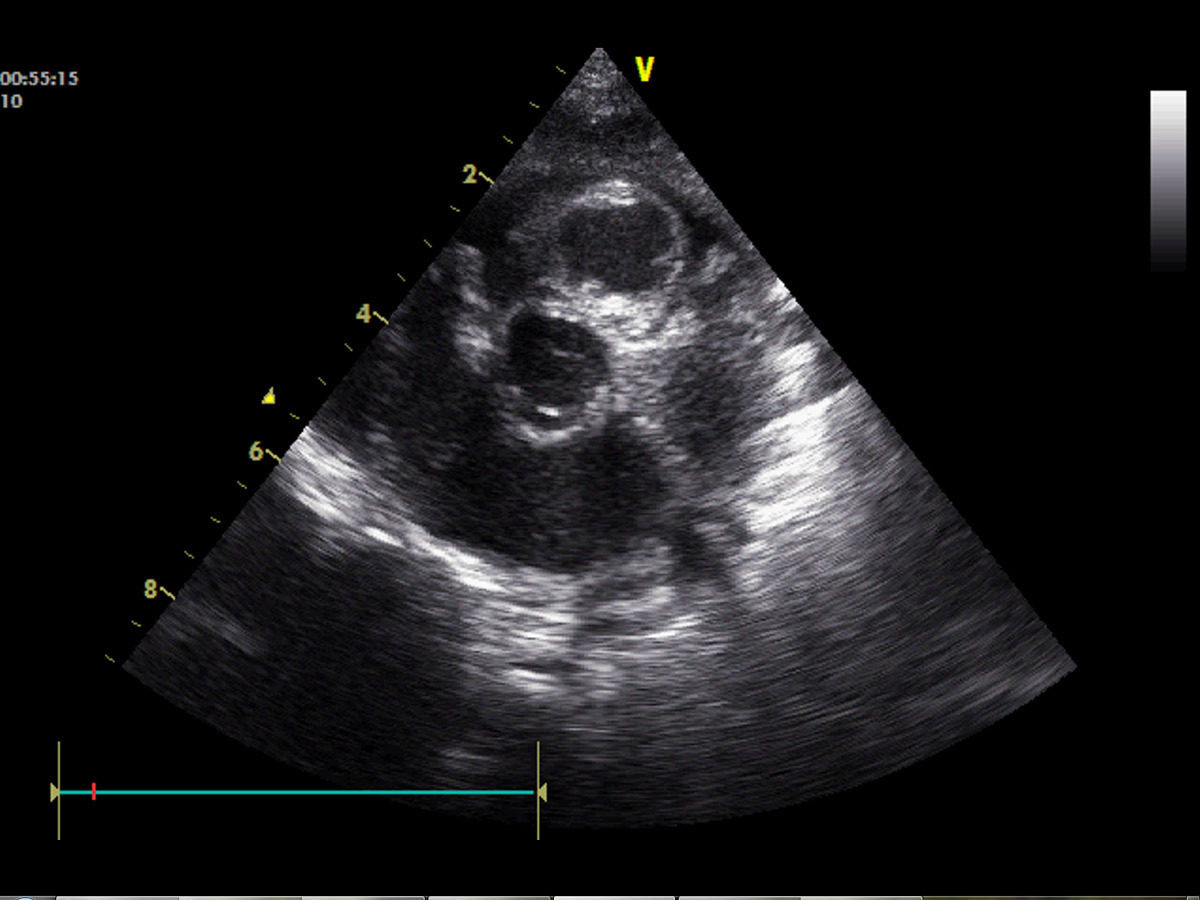

Certaines cardiopathies ne soufflent pas, d’autres soufflent plus tardivement (communication interventriculaire [CIV] par exemple).